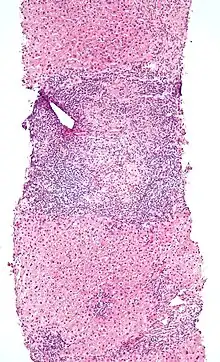

Micrograph of PBC showing bile duct inflammation and injury, H&E stain

On microscopic examination of liver biopsy specimens, PBC is characterized by chronic, nonsuppurative inflammation, which surrounds and destroys interlobular and septal bile ducts. These histopathologic findings in primary biliary cholangitis include:[32]

• Inflammation of the bile ducts, characterized by intraepithelial lymphocytes

• Periductal epithelioid granulomas.

• Proliferation of bile ductules

• Fibrosis (scarring)

The Ludwig and Scheuer scoring systems have historically been used to stratify four stages of PBC, with stage 4 indicating the presence of cirrhosis. In the new system of Nakanuma, the stage of disease is based on fibrosis, bile duct loss, and features of cholestasis, i.e. deposition of orcein-positive granules, whereas the grade of necroinflammatory activity is based on cholangitis and interface hepatitis. The accumulation of orcein-positive granules occurs evenly across the PBC liver, which means that staging using the Nakanuma system is more reliable regarding sampling variability.